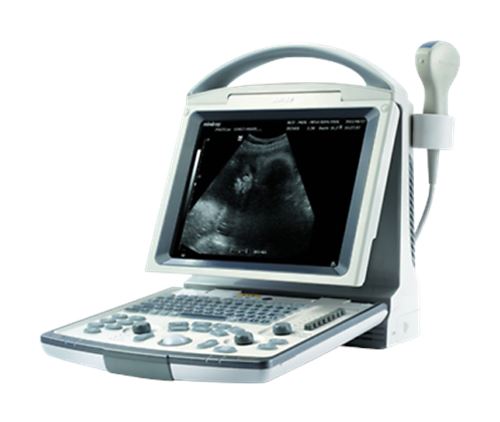

Veterinary Ultrasound K-DP-20Vet

Keebomed K-DP-20 is equipped with a best-in-class combination of performance and affordability. Provides the latest imaging technologies and convenient workflow options. Offers abundant measurement packages covering traditional ultrasound applications and emerging fields such as urology, MSK, and anesthesia.

- High resolution 12.1” LED with tilt functionality

- User-friendly keyboard and controls